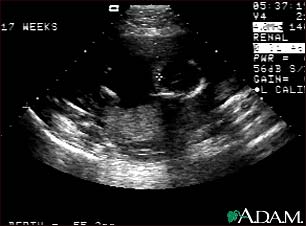

Ultrasound, normal fetus - ventricles of brain

This is a normal fetal ultrasound performed at 17 weeks gestation. The development of the brain and nervous system begins early in fetal development. During an ultrasound, the technician usually looks for the presence of brain ventricles. Ventricles are spaces in the brain that are filled with fluid. In this early ultrasound, the ventricles can be seen as light lines extending through the skull, seen in the upper right side of the image. The cross hair is pointing to the front of the skull, and directly to the right, the lines of the ventricles are visible.